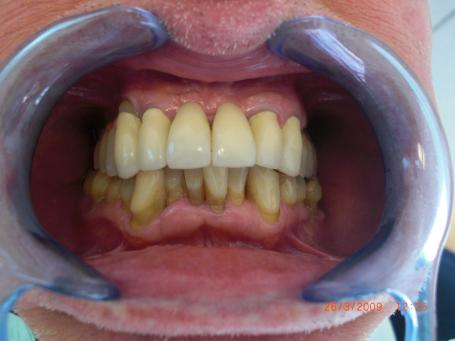

7°) Gencive artificielle en céramique rose

Une fausse gencive en céramique rose est réalisé dans le but de restaurer l’esthétique. Cela évite de faire des dents trop longues pour combler la perte osseuse dû aux précédentes extractions dentaires.

8°) Photo finale